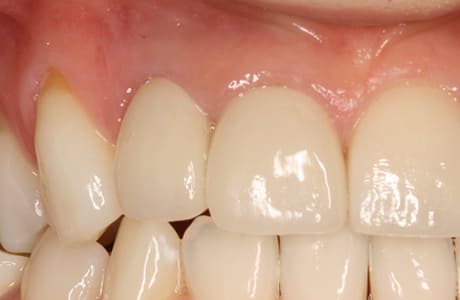

こちらが最終補綴物を装着した後の口腔内写真です。

初診時に見られた歯肉の炎症は改善し、健康的で引き締まった歯肉へと回復しています。

補綴物も高い透明感と自然な質感を備えており、審美性・機能性ともに理想的な仕上がりとなりました。